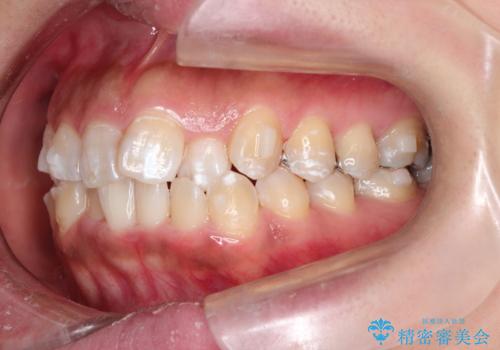

- 前歯のガタツキが気になると来院されました。

奥歯の噛み合わせは綺麗に噛んでいたため、前歯の叢生(でこぼこ)に集中して治療するように計画しました。

奥歯の噛み合わせは整っていたため、前歯の並びを美しく修正することに専念できました。